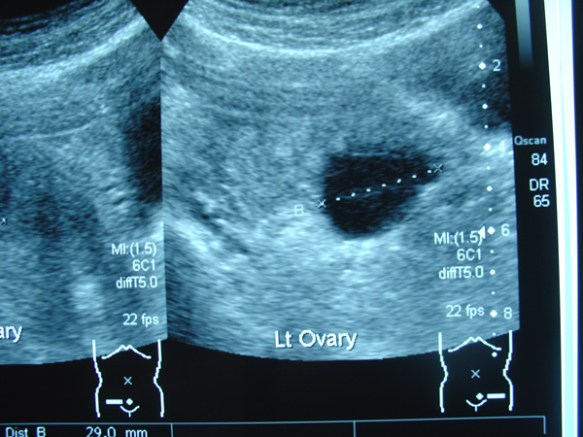

1. Scan in India in June 2011, showed bilateral ovarian cysts.

Right ovary: mass about 4.7 x 8.4 cm with both solid and cystic components seen. Ovary not seen separately.

Left ovary: mass about 8.5 x 5.2 cm with both solid and cystic components and ovary could not be visualised separately.

left-ovary